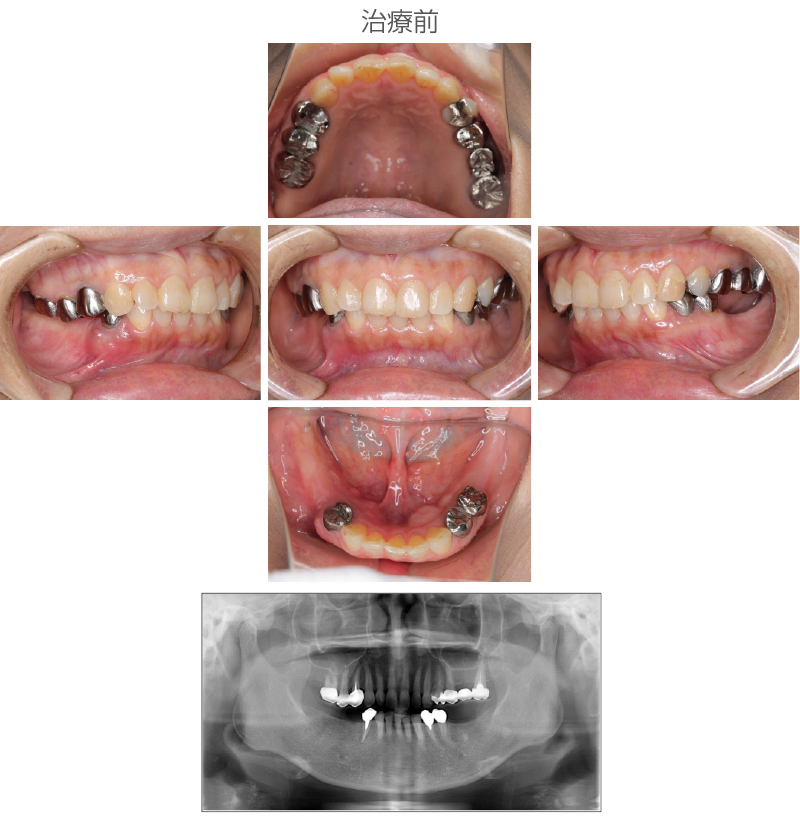

| 施術名 | インプラント治療(左上6番ソケットリフト 右下4番骨造成) |

|---|---|

| 施術の説明 |

インプラント治療とは、歯を抜いた所にチタン製の人工歯根を埋入し、新しく歯を入れる方法です。 今回のケースではソケットリフトにて骨造成をしました。 |

施術の副作用 (リスク) |

腫れや疼痛を感じる、違和感を感じるなどの症状を生じることがあります。 |

| 施術の価格 | 35万円~+消費税 |